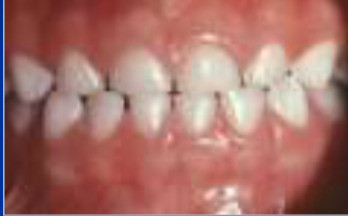

class II division 1

class II molar relationship, LABIOVERSION/flaring of maxillary incisors, steep curve of spee, and excess overjet

class II division 2

class II molar relationship, LINGUOVERSION of maxillary CENTRAL incisors,

and labioversion of maxillary lateral incisors

division 2

which class II division is moree likeely to havee an ACCEPTABLE FACIAL PROFILE and normall palatal width